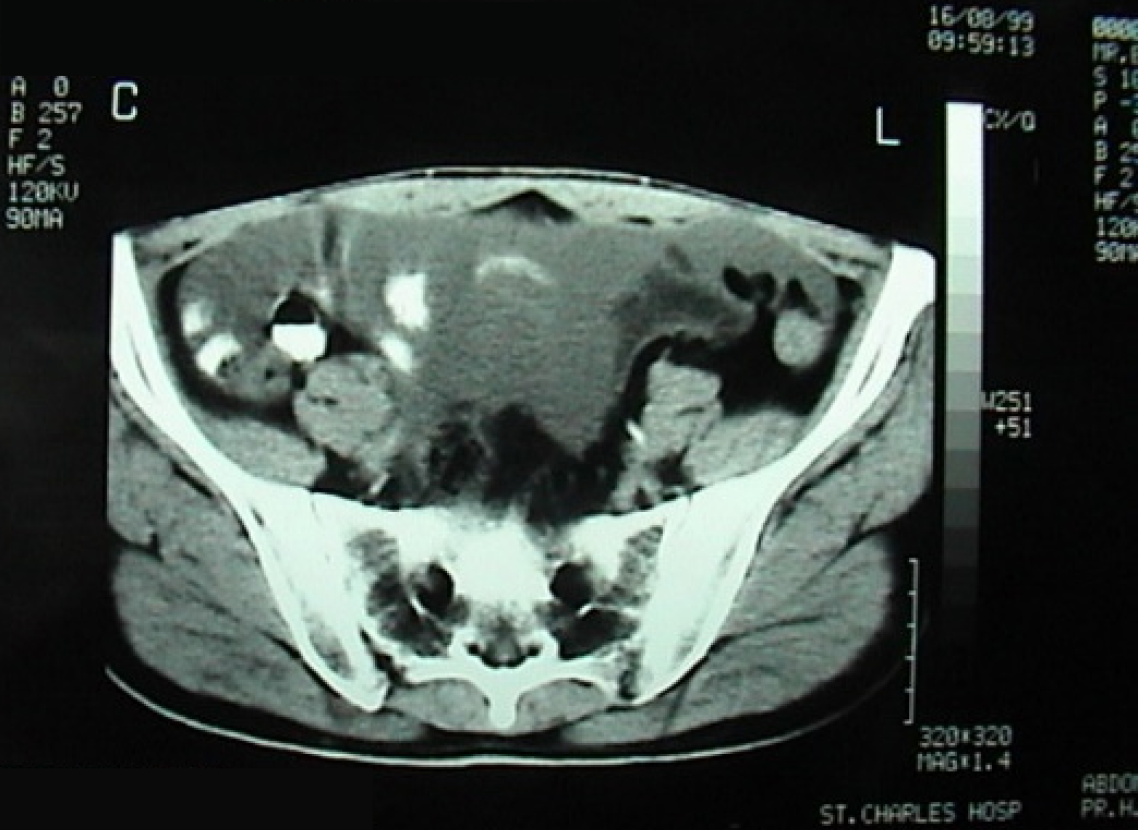

Figure 1 Enhanced computed tomography scan of the abdomen and pelvis showing a large amount of ascites.